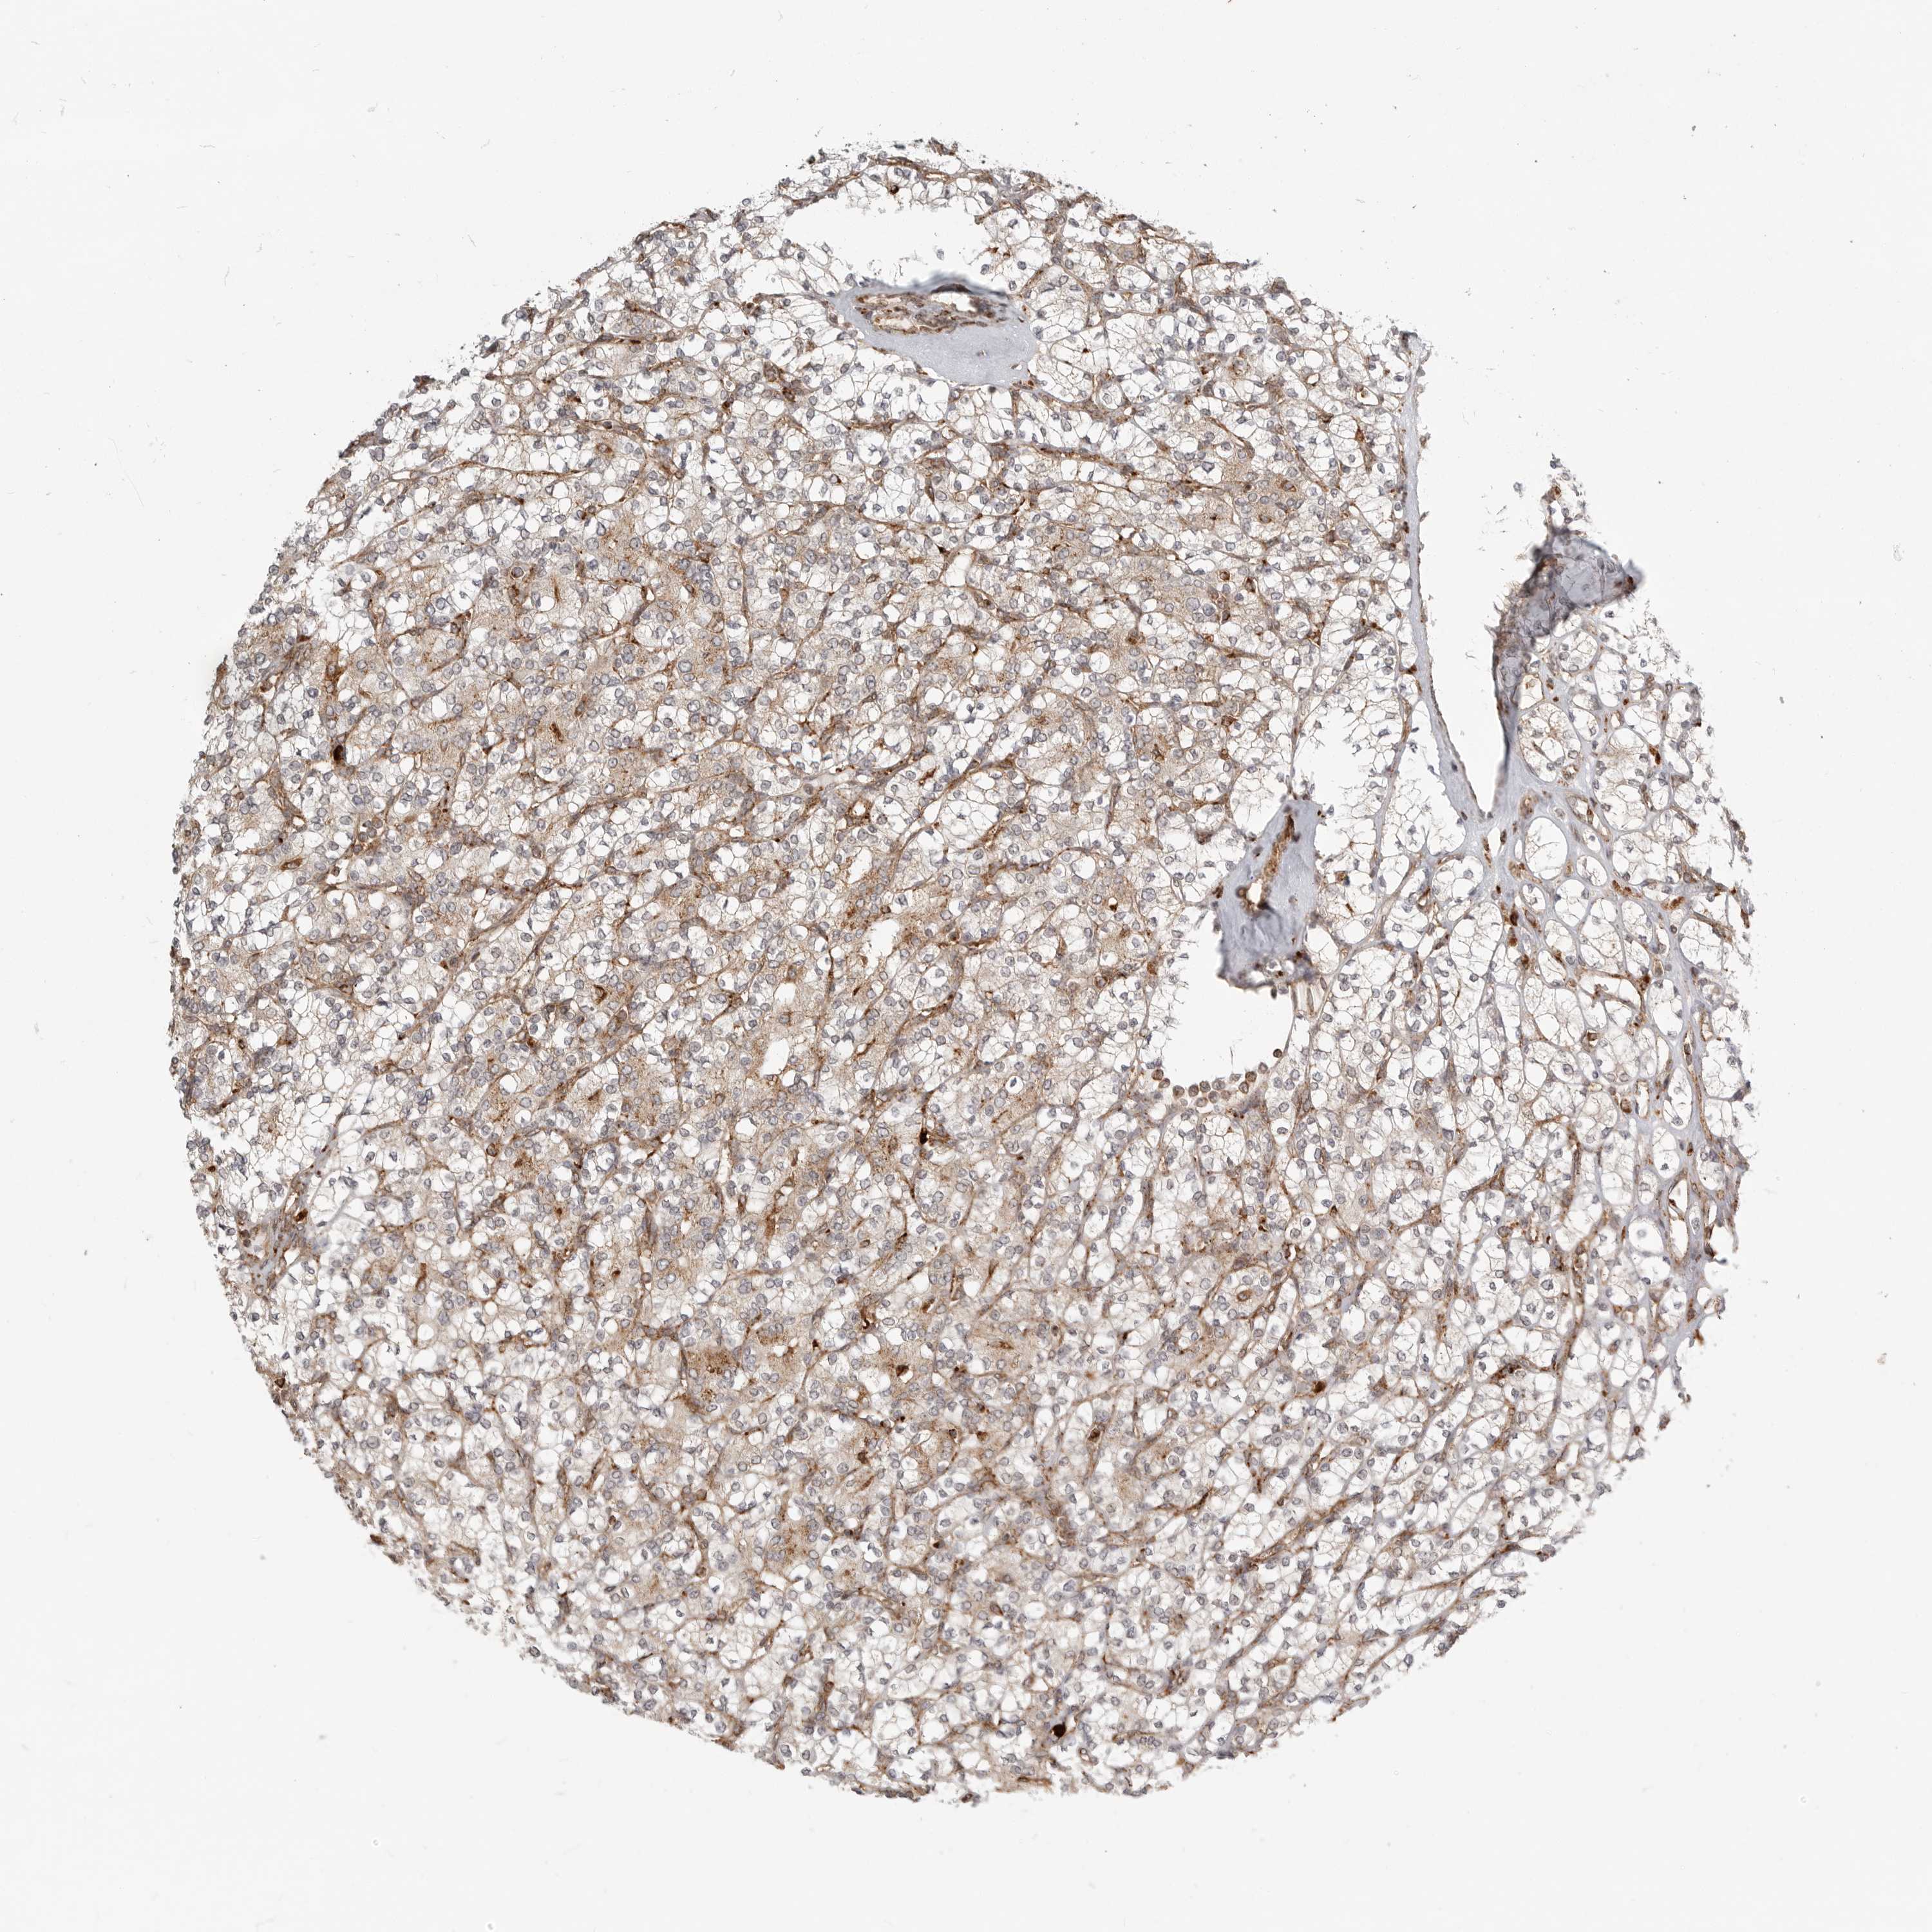

KIDNEY RENAL CLEAR CELL CARCINOMA (VALIDATION) - Interactive survival scatter ploti

The Survival Scatter plot shows the clinical status (i.e. dead or alive) for all individuals in the patient cohort, based on the same data that underlies the corresponding Kaplan-Meier plots. Patients that are alive at last time for follow-up are shown in blue and patients who have died during the study are shown in red.

The x-axis shows the expression levels (FPKM) of the investigated gene in the tumor tissue at the time of diagnosis. The y-axis shows the follow-up time after diagnosis (years). Both axes are complimented with kernel density curves demonstrating the data density over the axes. The top density plot shows the expression levels (FPKM) distribution among dead (red) and alive patients (blue). The right density plot shows the data density of the survived years of dead patients with high and low expression levels respectively, stratified using the cutoff indicated by the vertical dashed line through the Survival Scatter plot. This cutoff is automatically defined based on the FPKM cutoff that minimizes the p-score. The cutoff can be changed by dragging the vertical line or by entering a cutoff value in the square labeled "Current cut-off".

Under the Survival Scatter plot the p-score landscape (black curve; left axis) is shown together with dead median separation (red curve; right axis). Dead median separation is the difference in median mRNA expression between patients who have died with high and low expression, respectively. It is calculated as follows: median FPKM expression of dead patients with high expression - median FPKM expression of dead patients with low expression. This is intended to aid the user in visually exploring custom cutoffs and the associated p-scores and dead median separation.

Individual patient data is displayed and can be filtered by clicking on one or more of the category buttons on the top of the page. Categories describing expression level and patient information include: high, low, alive, dead, female, male and tumor stages. The scale of the x-axis can be toggled between linear and log-scale by clicking on the "x log" button. Mouse-over function shows TCGA ID, patient information and mRNA expression (FPKM) for each patient.

& Survival analysisi

Kaplan-Meier plots summarize results from analysis of correlation between mRNA expression level and patient survival. Patients were divided based on level of expression into one of the two groups "low" (under cut off) or "high" (over cut off). X-axis shows time for survival (years) and y-axis shows the probability of survival, where 1.0 corresponds to 100 percent.

IDUA is not prognostic in Kidney Renal Clear Cell Carcinoma (validation)

Best expression cut offi

: 7.91

Average pTPM 10.7

Number of samples 100